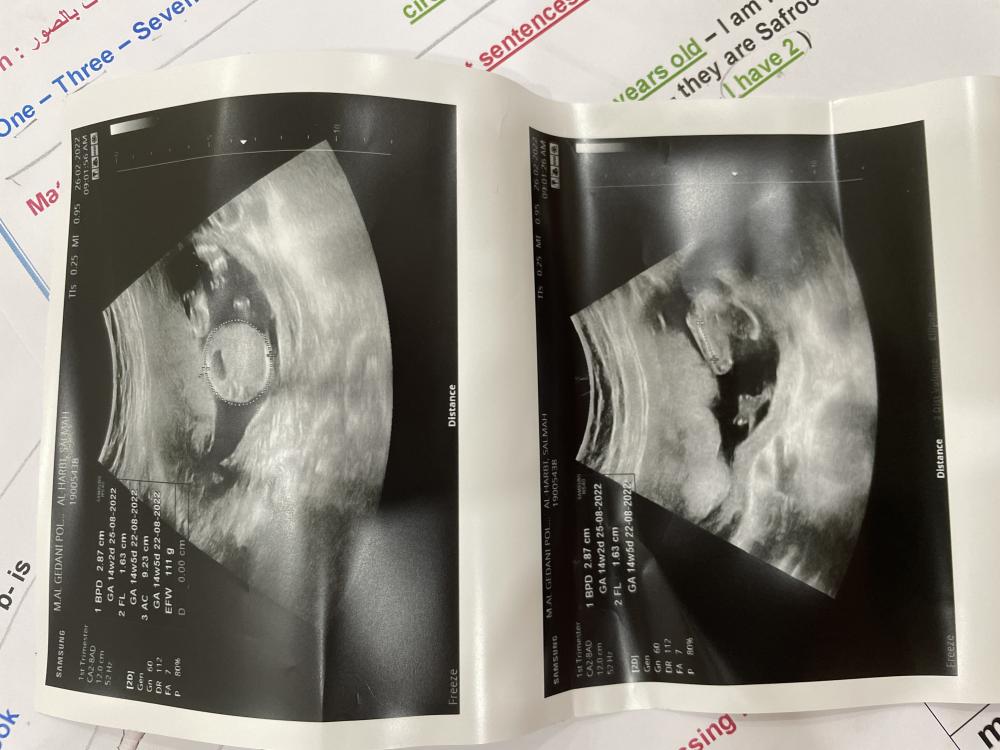

السلام عليكم رحت مستوصف خاص بعرف جنس الحنين واخرتها تقول مو باين بنزل الصور والا تعرف تقلي

مع الاسف الصوره مو موضحه وش بين الارجل